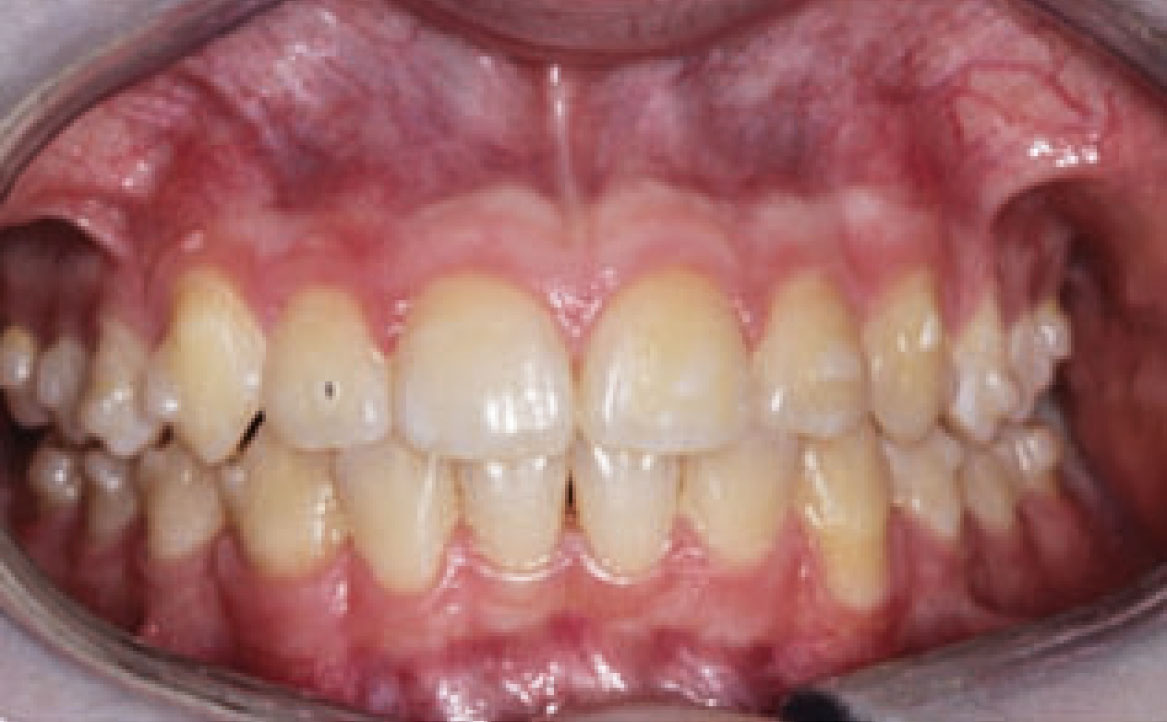

Dall’esame obiettivo intra orale si osservava una seconda classe canina destra e sinistra, una seconda classe molare destra e sinistra, e un diametro inter-canino e inter-molare ridotto sia in riferimento al mascellare superiore sia al mascellare inferiore (fig. 3A-3E).

A seguito del trattamento è stato osservato un miglioramento dell’igiene orale (fig. 5).